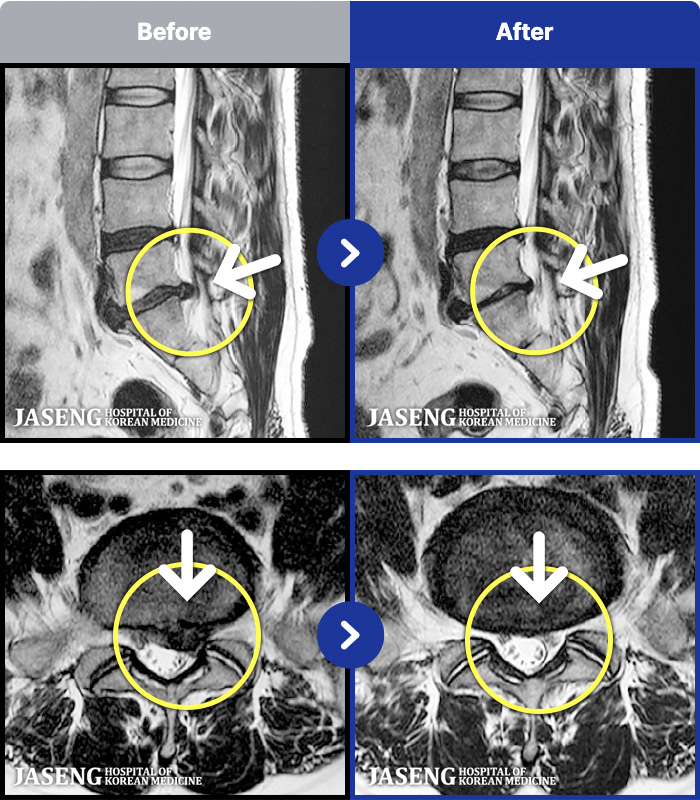

1,298 MRI ũ ʸ Ȯϼ.

[] 23.11.11~25.06.04